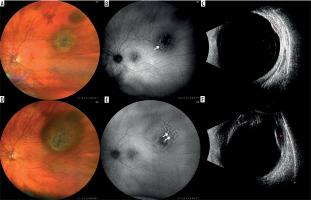

Figure 1

Nevus with a documented growth into a melanoma in a 72-year-old patient within 9 months. The lesion was observed for more than 10 years and no features of progression were detected: A) color fundus photography of the observed nevus; B) fundus autofluorescence. photography showing mildly hyperautofluorescent drusen (arrow); C) ultrasound image showing mildly hypoechogenic lesion (red asterisk); D) color fundus photography after 9 months with evident growth; E) fundus autofluorescence photography of the newly appeared orange pigment in the upper portion of the lesion (double arrow); F) ultrasound image of growing hypoechogenic lesion (red asterisk)